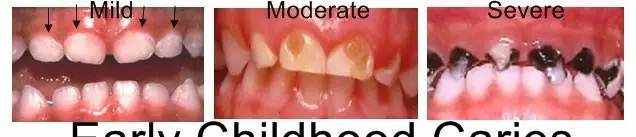

婴幼儿不会患龋

大误解。

乳牙也会患龋。如果不治疗的话,还会影响其它牙齿甚至可能对恒牙产生不利影响。